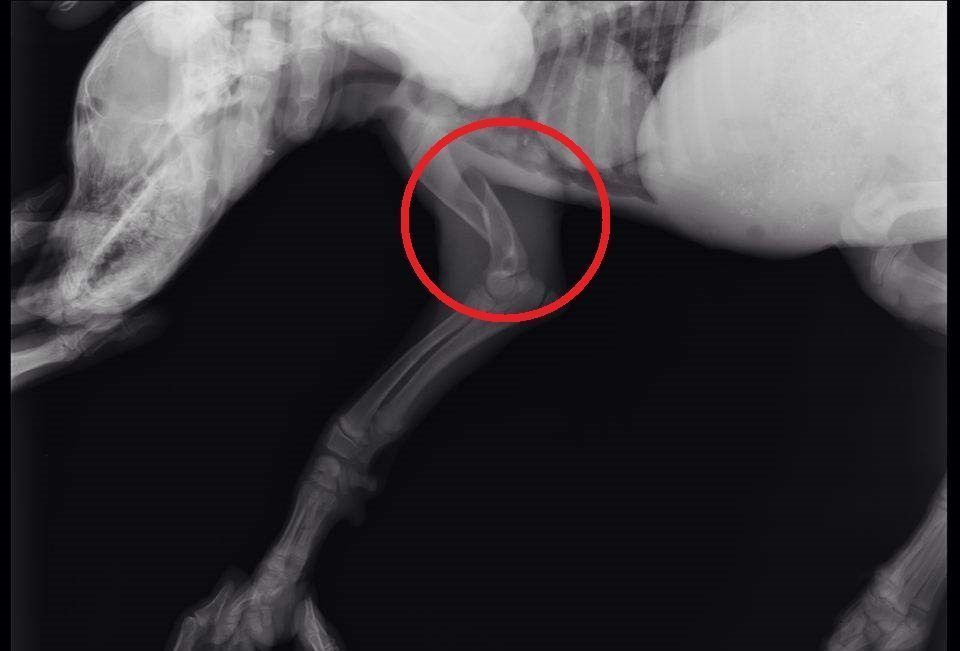

Το κουταβάκι που βλέπετε στις φωτογραφίες εντοπίστηκε χθες στο Άκτιο να κλαίει από τους πόνους κοντά στα διόδια της υποθαλάσσιας σήραγγας καθώς όπως αποδείχτηκε έχει σπασμένα τα δύο πόδια του ενώ είναι χτυπημένο και στην κοιλιά. Το πως τραυματίστηκε το ζώο παραμένει άγνωστο αν και σύμφωνα με τον κτηνίατρο Νίκο Ρώσσο, που το εξέτασε, κάποιος είναι πολύ πιθανό να το το κλώτσησε.

Η Δώρα Τσάτση μέλος του σωματείου «Παρέμβαση για τα Ζώα - Πρέβεζα» εξήγησε στο www.zoosos.gr ότι ο κ. Ρώσσος τους είπε πως είναι απίθανο το κουταβάκι, που ζυγίζει μόλις τέσσερα κιλά, να χτυπήθηκε από όχημα καθώς δεν έχει σημάδια και αυτά τα τραύματα προκαλούνται μόνο από κλωτσιά.

Εξαιτίας του νεαρού της ηλικίας του κουταβιού δεν θα γίνουν όλες οι επεμβάσεις ταυτόχρονα. Αρχικά θα χειρουργηθεί στην κοιλιά και στην συνέχεια θα ακολουθήσουν οι επεμβάσεις στο πίσω πόδι του που έχει σπάσει σε δύο σημεία και στη συνέχεια στο μπροστινό.